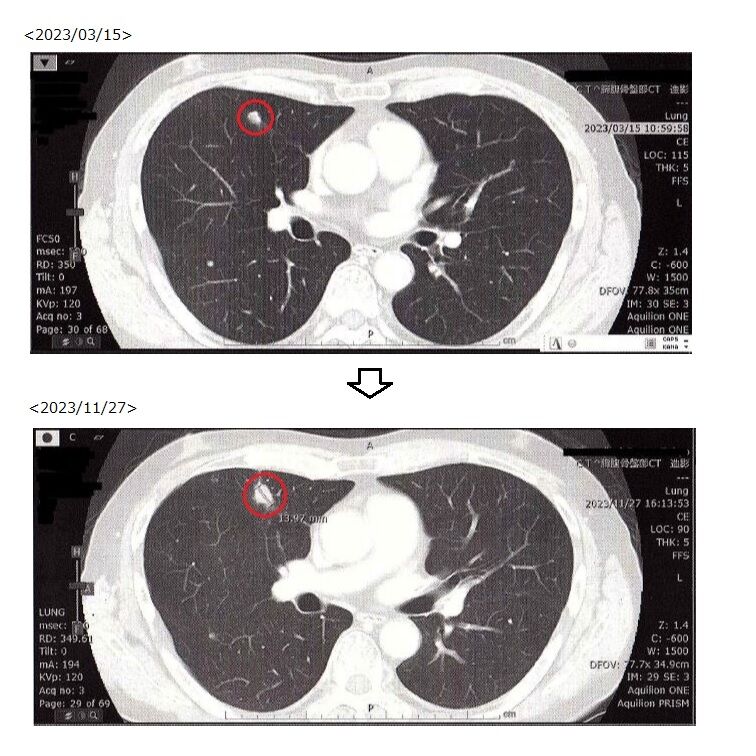

治療は正月明けに開始となります。がんがまた小さくなってくれればと願うばかりです